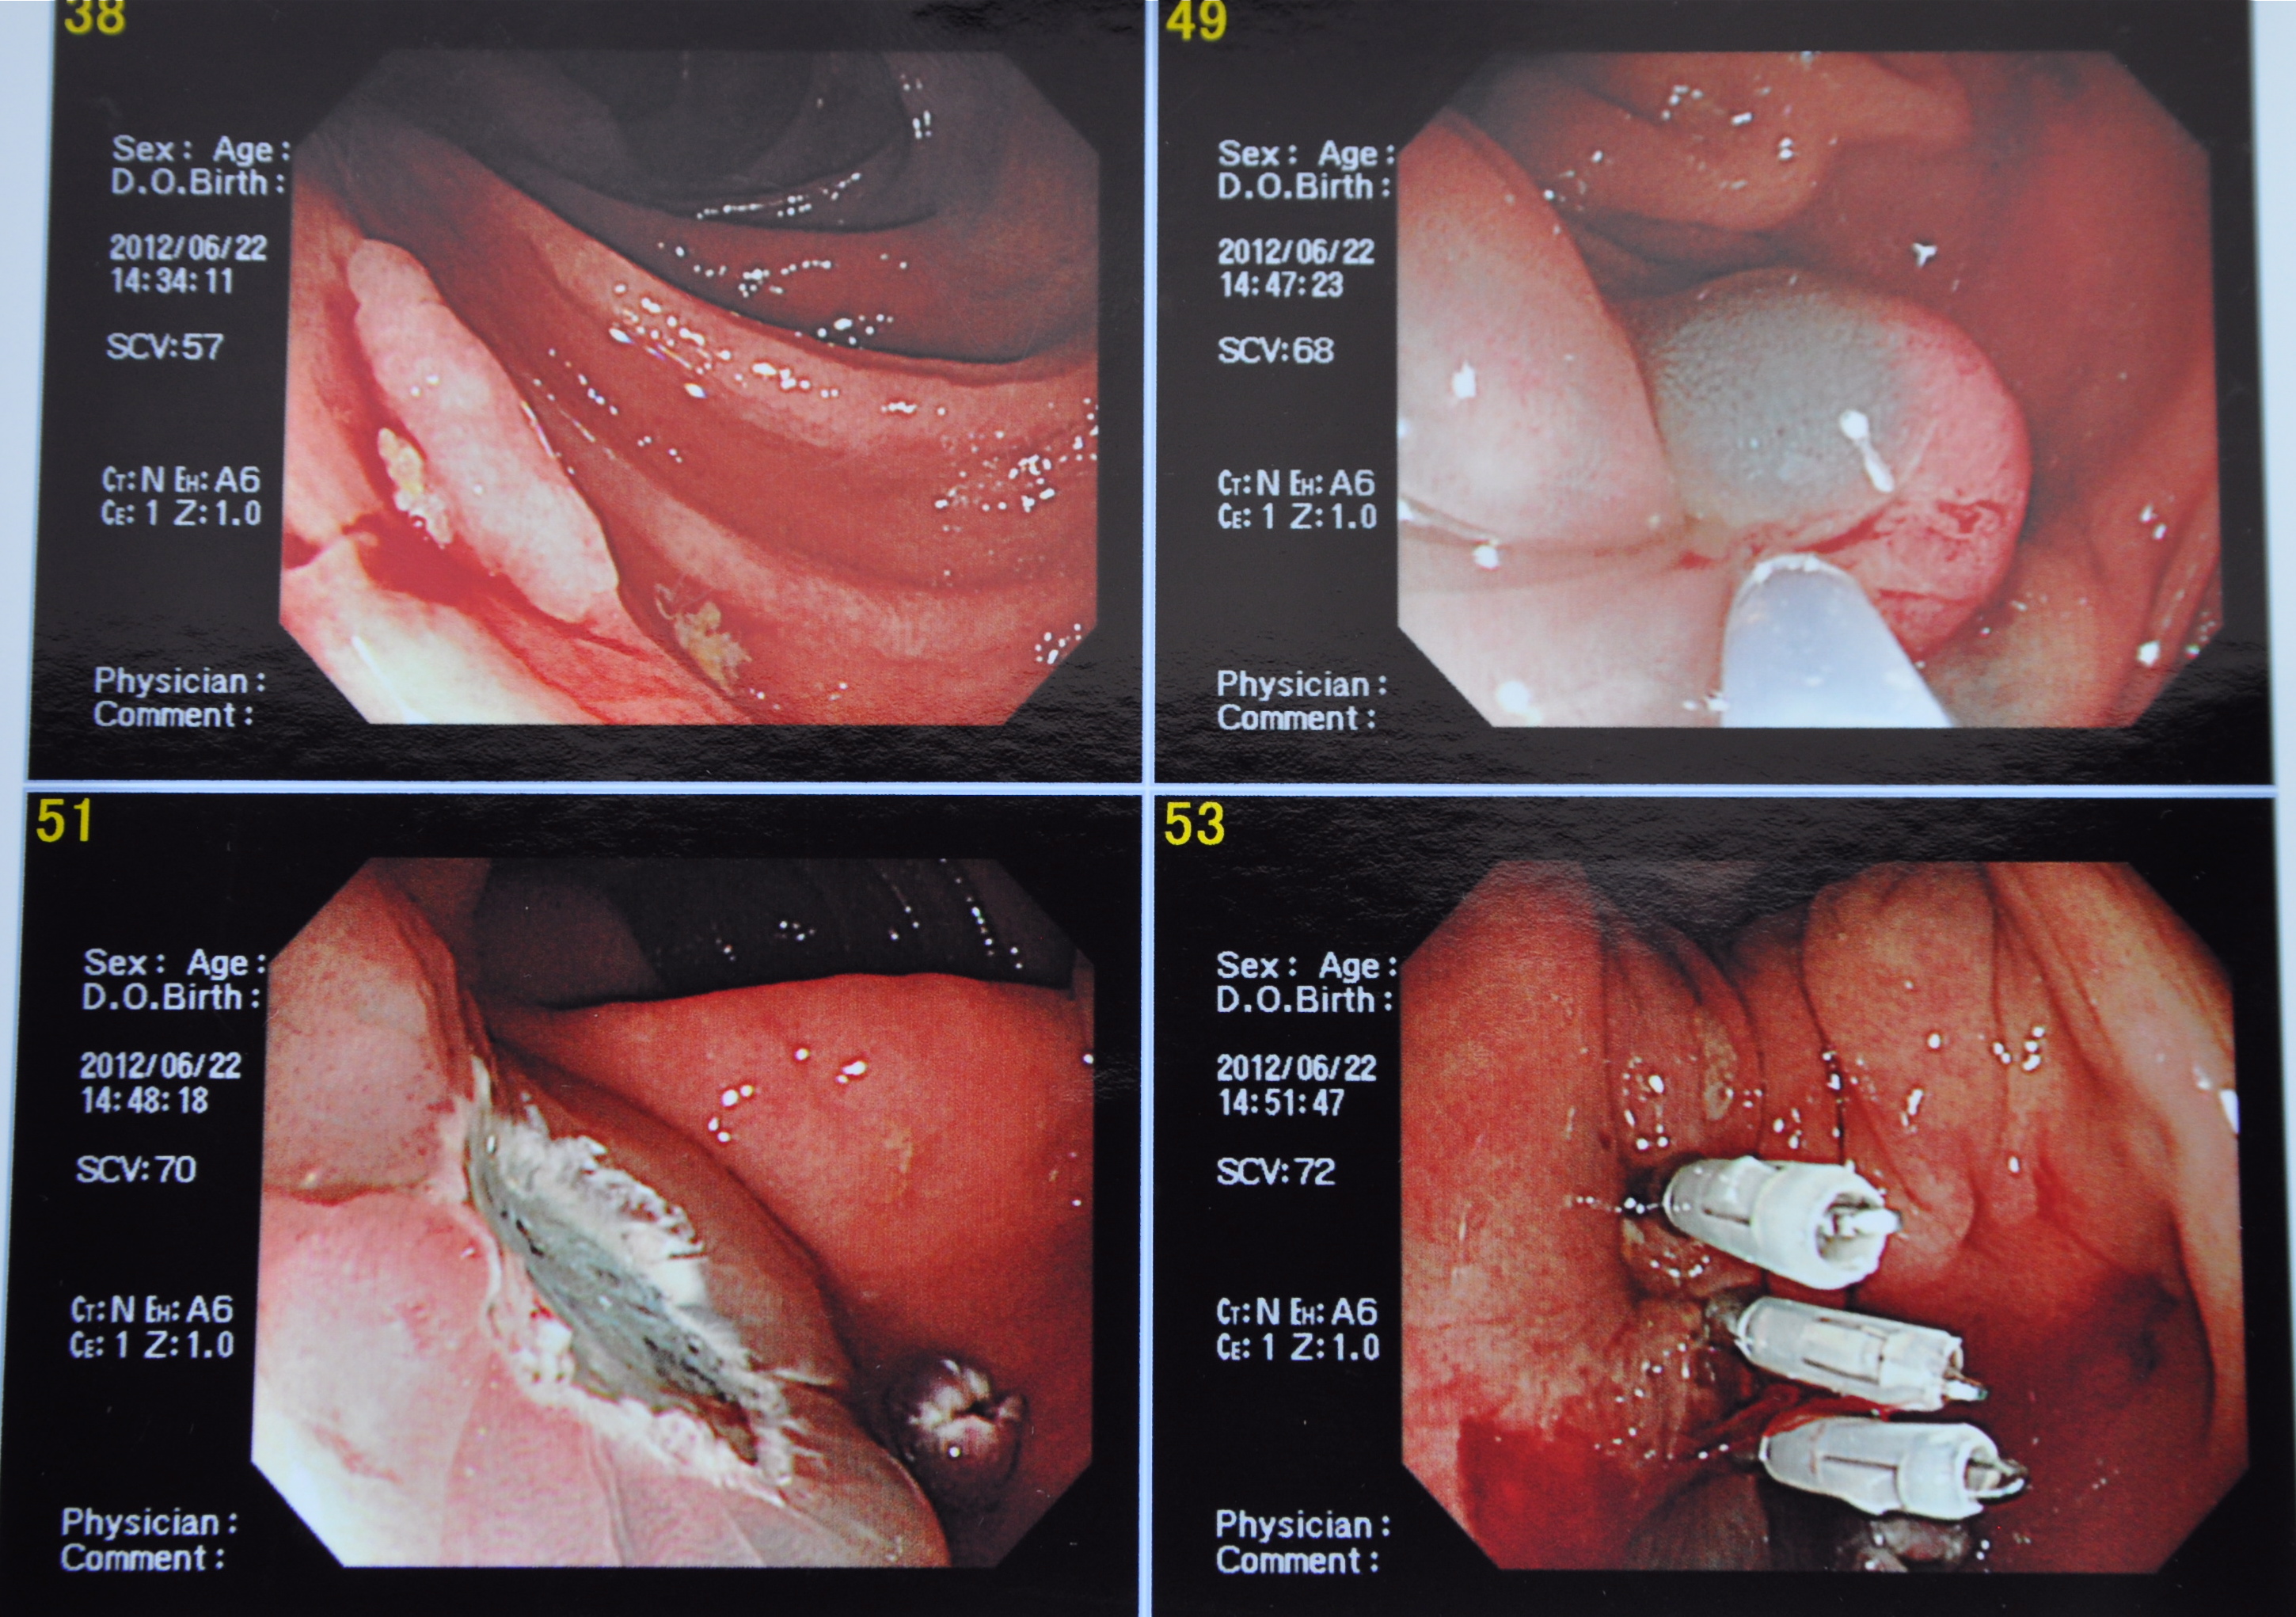

Travel log along my colon. Getting ready to snip minor offenders. 48 shows electrical snare being wound around big boy polyp.

Kubota-sensei progresses up my colon occasionally halting to snip off some junior polyps until he comes to the big boy polyp. The technique is to inject what he calls ‘blue water’ in the tissue under the polyp and by so doing elevate and expose the the object of desire. An electrical snare is then wound around it and the offending growth is burnt off. The wound is then closed with clip things that are part of the tool kit.